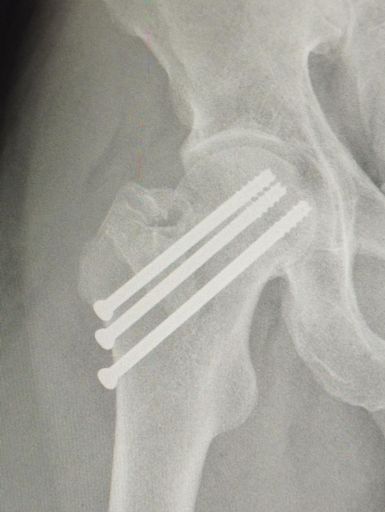

4 meses y 3 tornillos después, con unos kilos de mas y la mejor compañía 😅😅